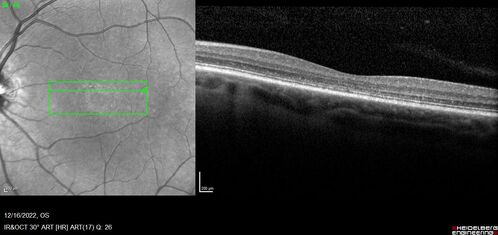

Stargardt Disease - Very Mild - 24 year old

This patient has 3 different ABCA4 mutations. His mother and sister have stargardts and his father has RP. His sisters images are also on Retinagallery.com